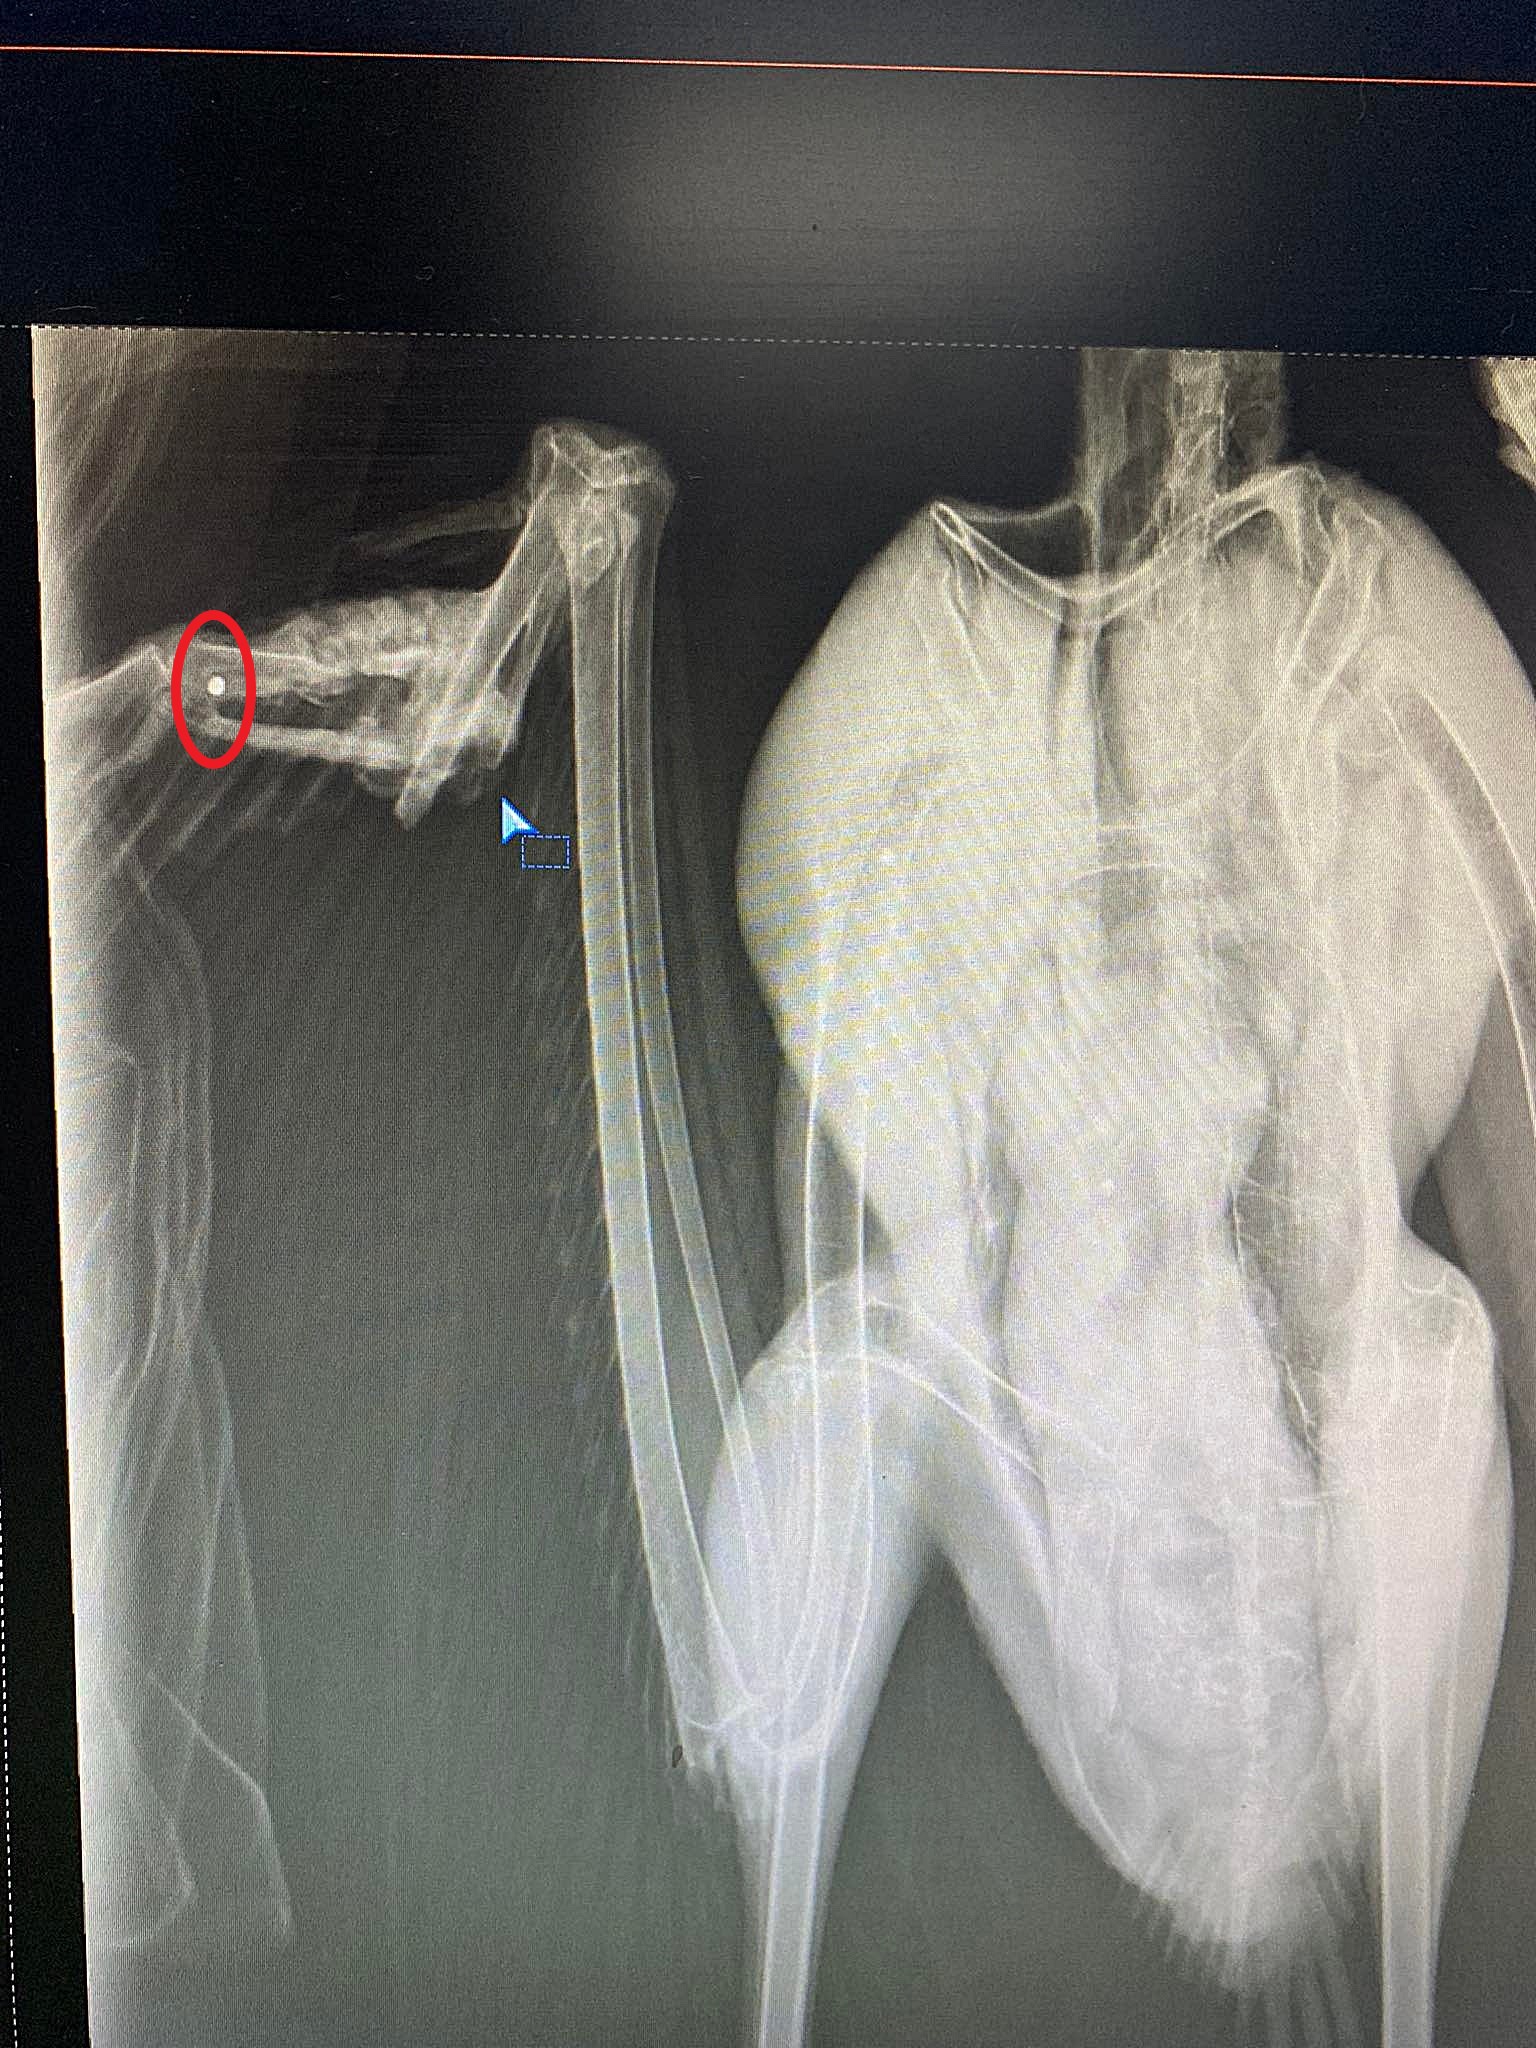

Αλγεινή εντύπωση έχουν προκαλέσει δύο περιστατικά με πυροβολημένα πουλιά που μεταφέρθηκαν πριν από λίγες μέρες στον Σύλλογο Προστασίας και Περίθαλψης Άγριας Ζωής.

Ο λόγος για έναν νεαρό πετρίτη και έναν πελαργό που εστάλησαν αντίστοιχα στις 8 και 12 Νοεμβρίου από το Δασαρχείο Χανίων, και τα δυο πουλιά πυροβολημένα.

Και με τόσο σοβαρά κατάγματα που δεν θα γυρίσουν ποτέ στην άγρια φύση, σύμφωνα με τους ειδικούς που εκφράζουν τον προβληματισμό τους...